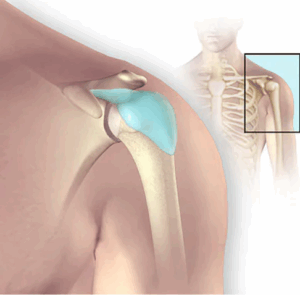

Bursitis

Bursitis (bur-SY-tis) is a painful condition that affects the small, fluid-filled sacs — called bursae (bur-SEE) — that cushion the bones, tendons and muscles near your joints. Bursitis occurs when bursae become inflamed.